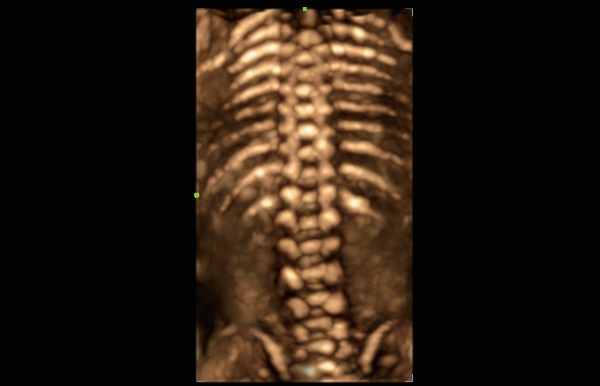

Soluzioni di diagnostica per immagini complete con tecnologia ZST+

La piattaforma ZST+ è un'innovazione straordinaria, che rappresenta un'evoluzione nel campo dell'ecografia. Grazie alla trasformazione delle metriche a ultrasuoni dal beamforming convenzionale all'elaborazione basata sui dati di canale, supera la tradizionale limitazione del trade-off tra risoluzione spaziale, risoluzione temporale e uniformità dei tessuti, offrendo una qualità d'immagine eccezionale per infinite soluzioni di imaging con miglioramenti continui.